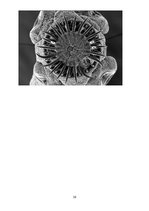

10.1.Lenteņi (morfoloģija): ķermenis ir lentveida saplacināts. Šie tārpi sastāv no galvas, kakla un ķermeņa jeb strobils, kas ir sadalīts posmos jeb proglotīdos. Ķermeņa garums dažām sugām variē no dažiem mm līdz pat 10 un vairāk metriem. Tas sastāv no viena vai vairākiem tulkstošiem proglotīdu. Uz galvas jeb skoleksa ir piestiprināšanās aparāts, kuram bieži ir kāši, lai tārps drošāk nostiprinātos. Kakls ir jaunu posmu veidošanās vieta. Katrā proglatīdā atrodas nervu sistēmas, …